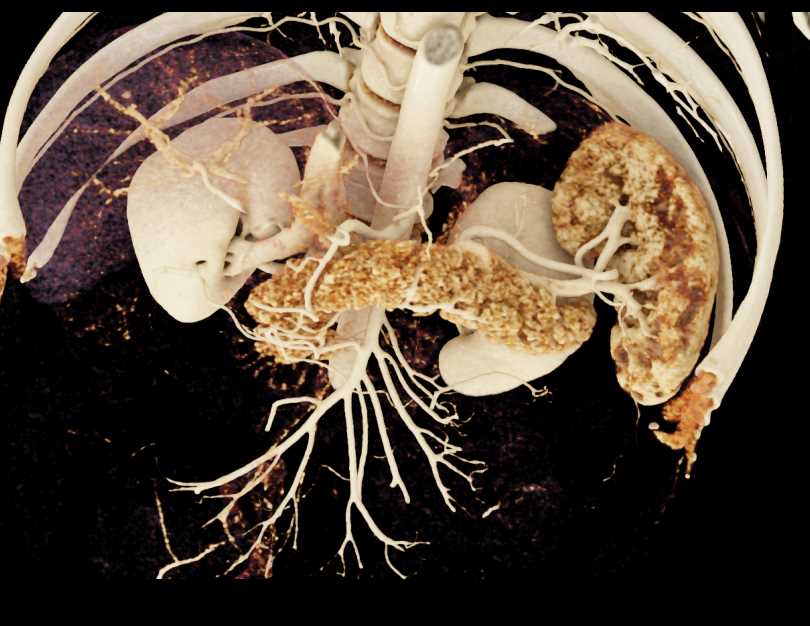

Subtle Neuroendocrine Tumor Body of Pancreas